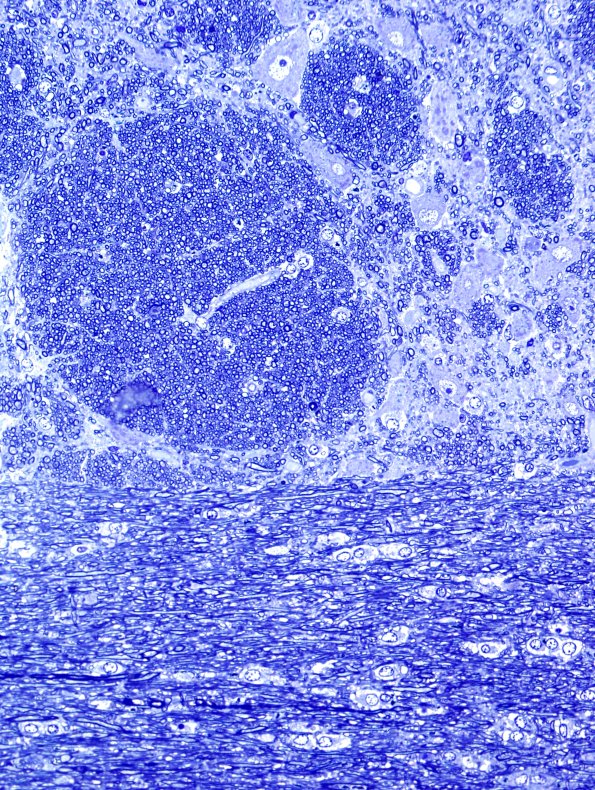

The pontine basis is shown in this one-micron thick toluidine blue stained plastic embedded section.